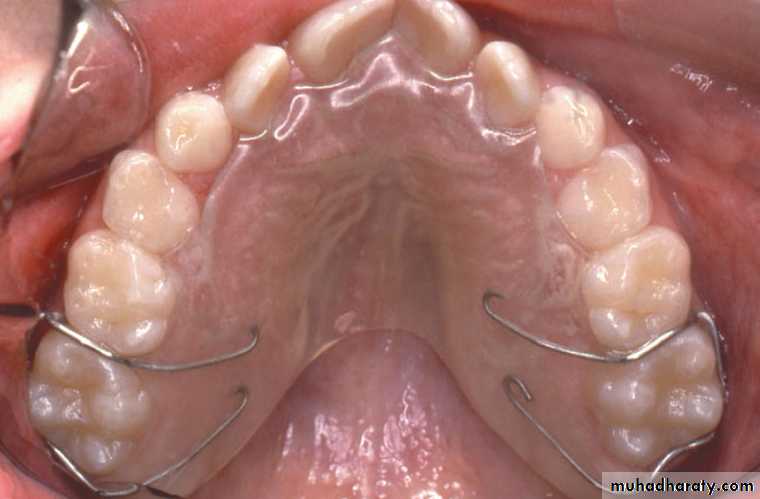

The preferred appliance is adjustable lingual arch that is banded to molars and requires little patient cooperation.

• W arch and quad helix are reliable and easy to use.

Both are constructed from 0.9 mm stainless steel wire and can be adjusted to produce anterior or posterior expansion.

The lingual wire should contact the teeth involved in crossbite.

The appliance is activated by opening it 3-5 mm wider than passive width.